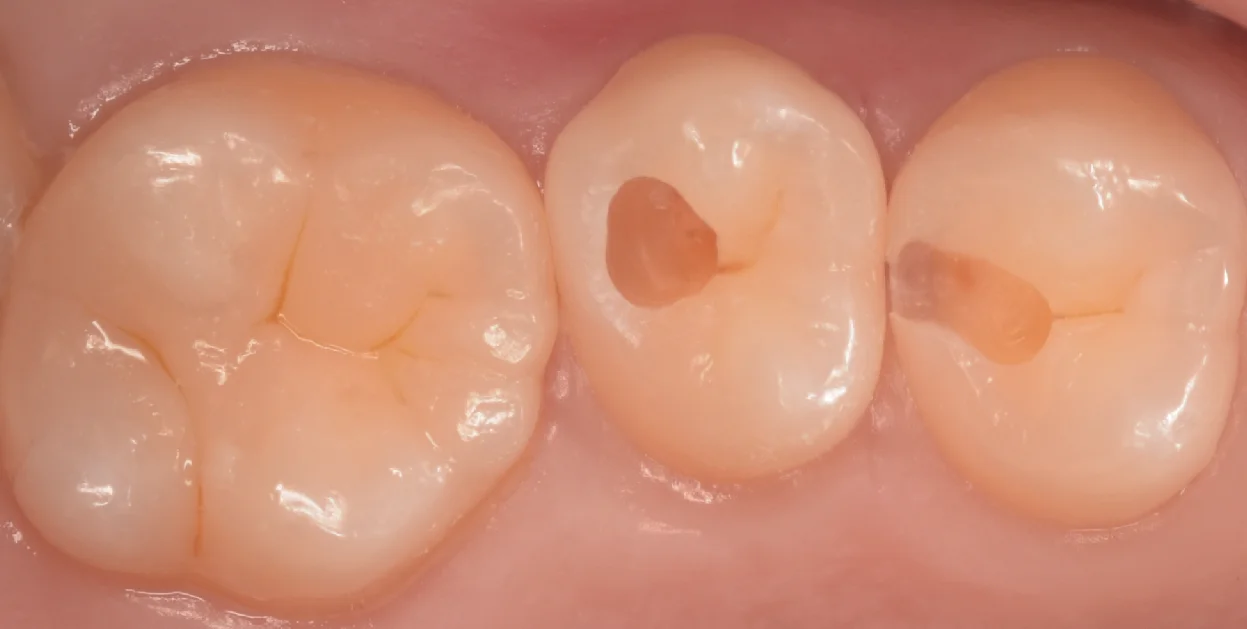

虫歯を取り切ったのがこちらになります。

真ん中の歯は特に内部で大きくなっていて、画面で見て左上1/4は内部が完全にない状態になっています。

歯の表面のエナメル質という層だけが残っている状態になりますね。

そしてこう言う感じで歯を温存できるのがこのダイレクトボンディング最大のメリットですね。

間接法(型取りして、次のタイミングで出来たものをつける)方法の場合、これほど薄く残存している歯は後々割れてくるリスクを鑑みて削ってしまうことが多いです。